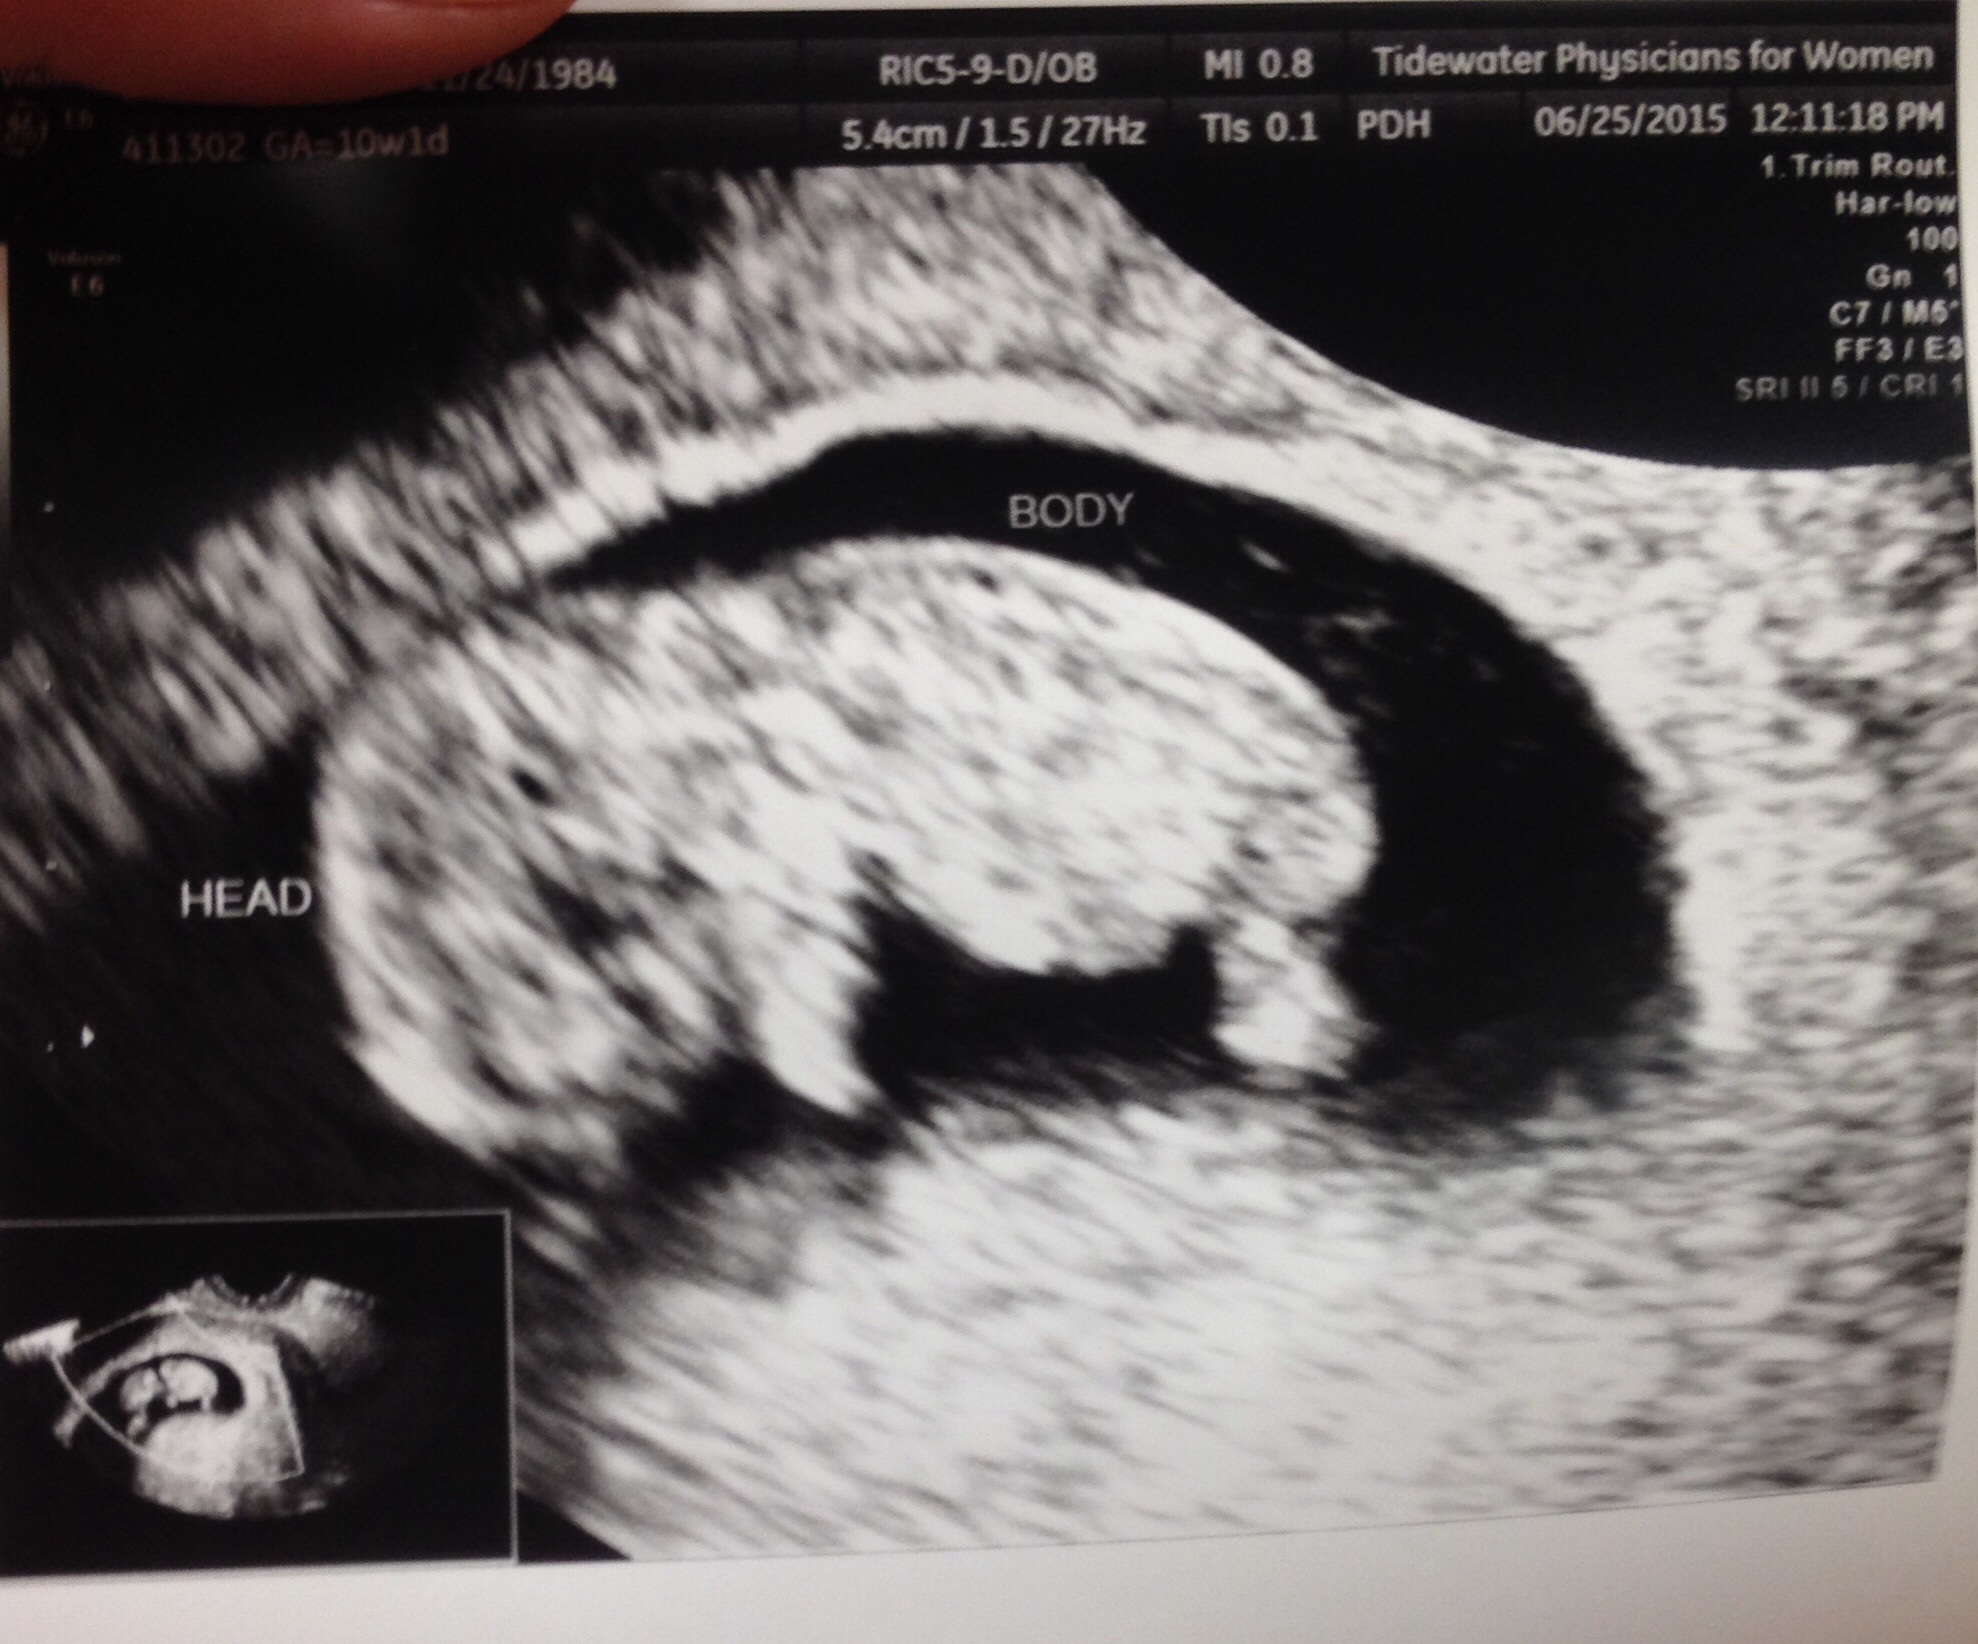

• Sleepy and getting full so quickly. Other than that, I'm great! I saw my little one today :)